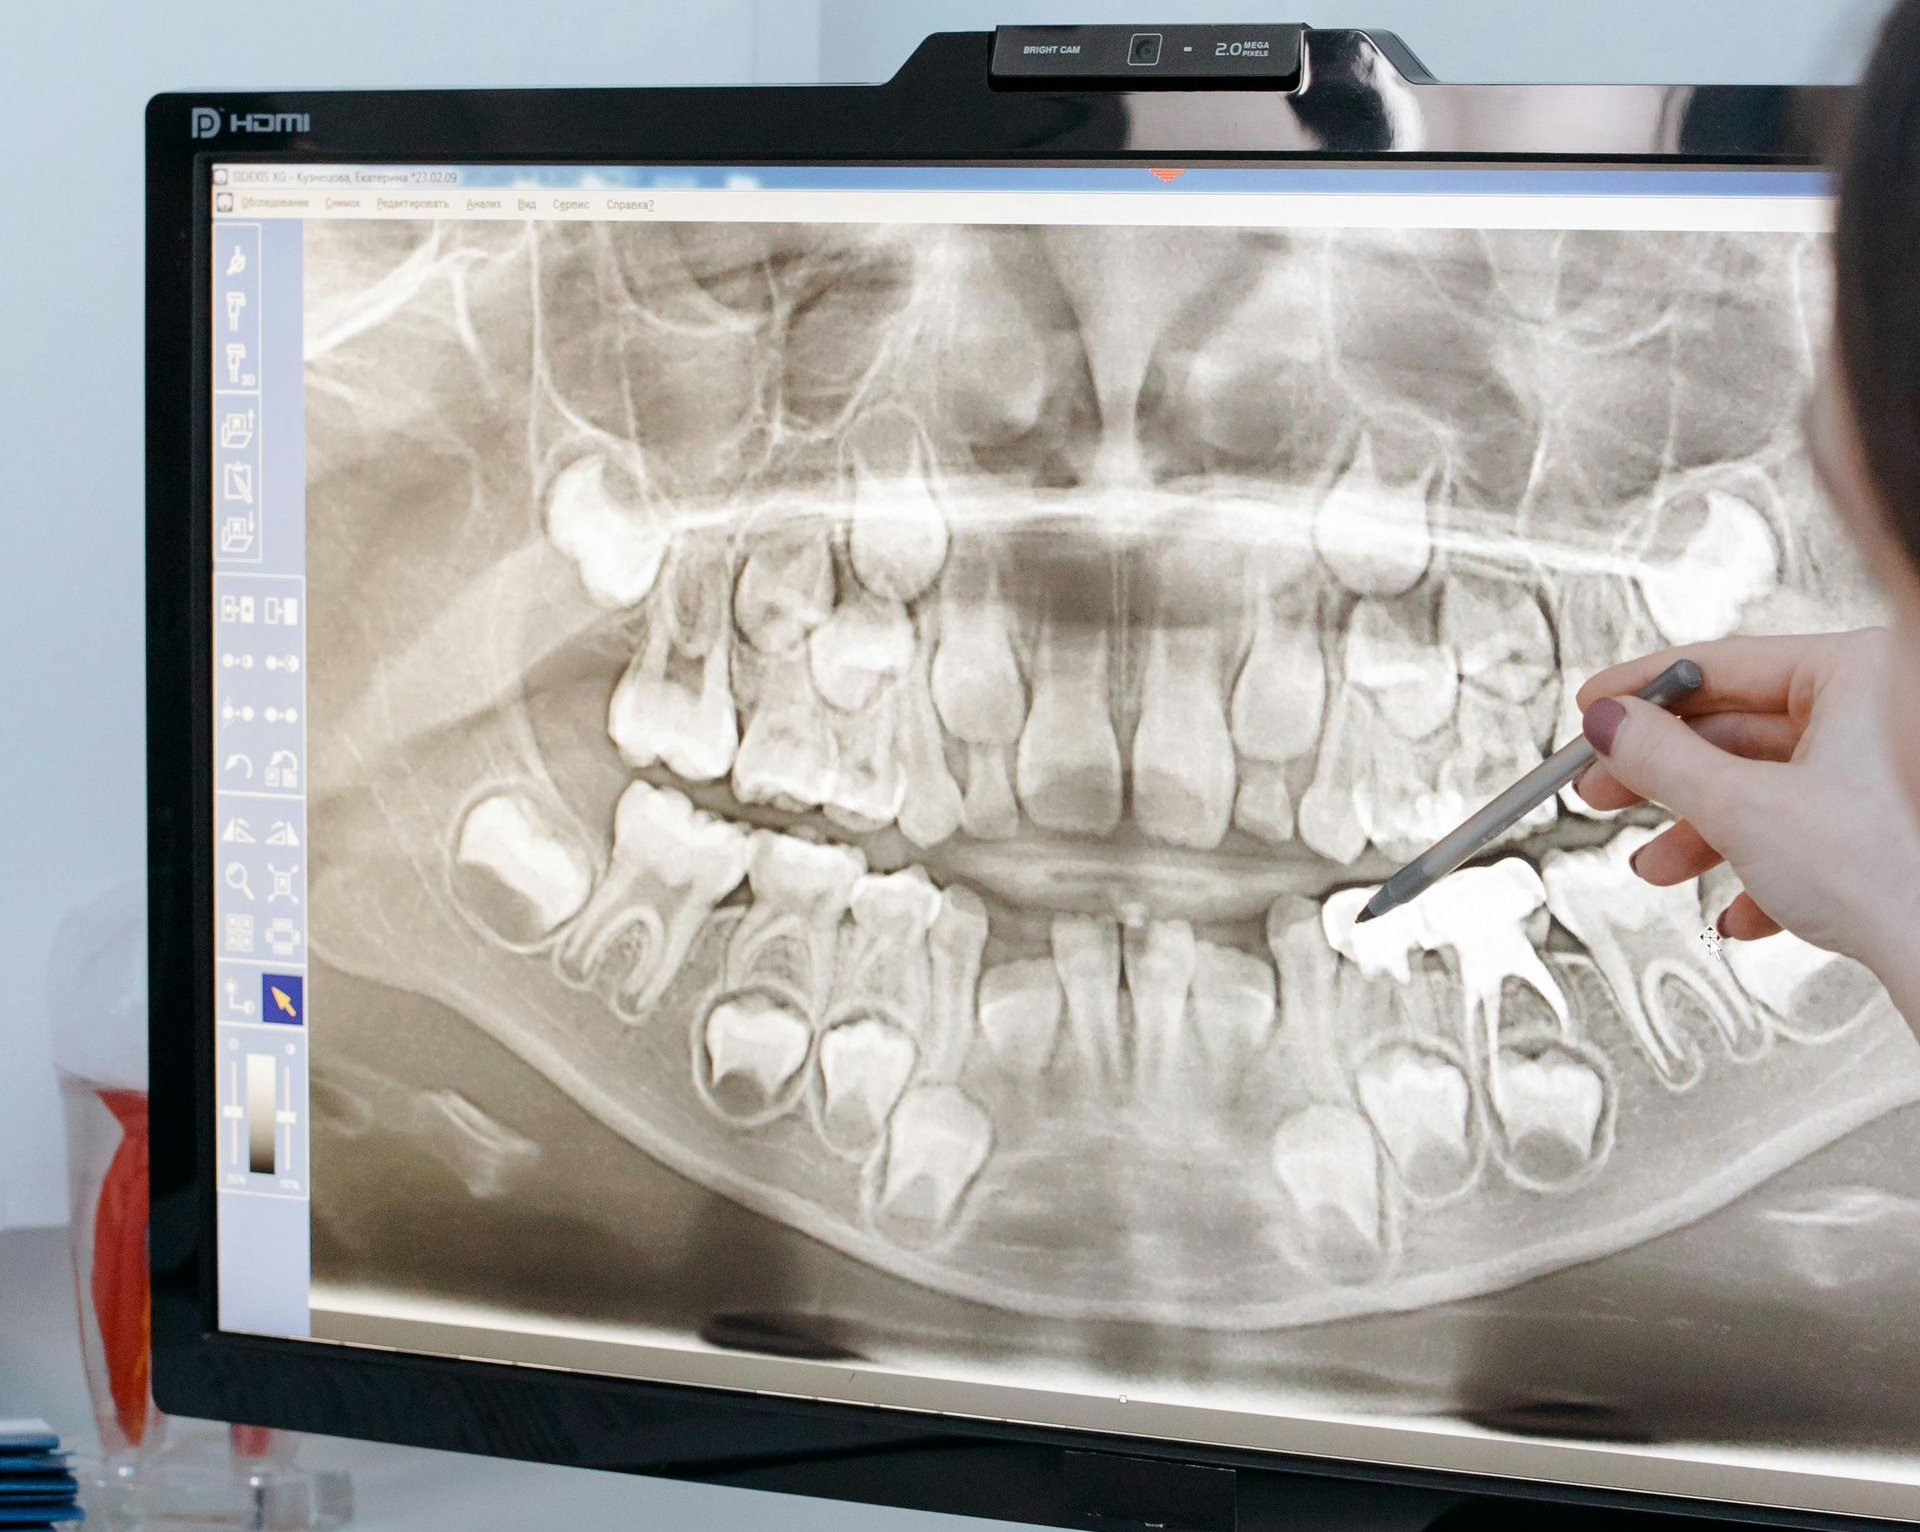

Why Digital X-rays?

PRECISION X-RAYS, SAFER FOR YOU

Digital X-ray technology allows us to capture clear, detailed images while exposing patients to significantly less radiation (up to 80%) than traditional film X-rays. Because digital sensors are much more sensitive than film, they require far less radiation to produce high-quality images.

The reduces exposure makes digital X-rays a safer option for patients of all ages, especially children and those who require frequent imaging as part of their dental care.